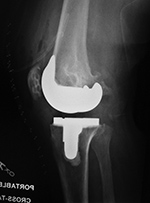

Unicompartmental knee prosthesis placed in lateral knee compartment |

50 year-old man with lateral knee compartment degenerative osteoarthritis |